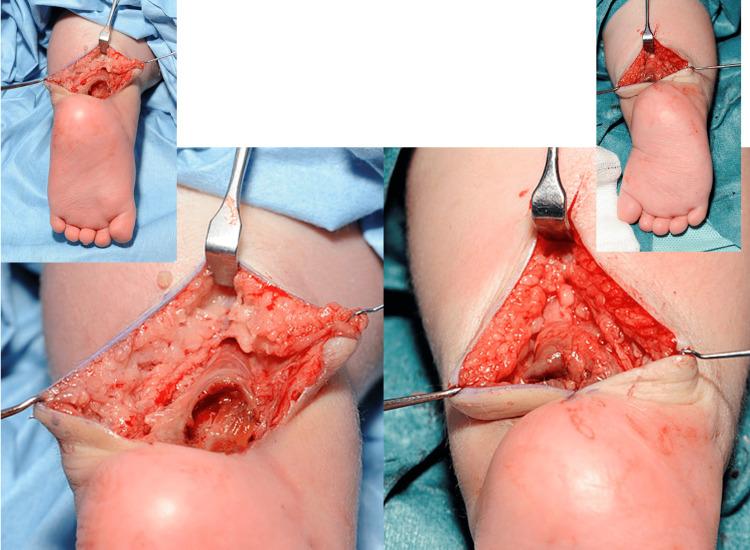

Pseudoaneurysm following percutaneous tendoachilles (TA) tenotomy is a rare complication found in children with congenital talipes equinovarus (CTEV). It is postulated that associated aberrant vascular anatomy in combination with CTEV may be the underlying aetiology. In this case report, we describe a case of a toddler who developed bilateral pseudoaneurysms following percutaneous tendoachilles tenotomy and explore the management and outcome in relation to this. Based on this case report and a review of the literature, the consistent clinical findings of swelling and/or discolouration due to pseudoaneurysm occur at three weeks post-tenotomy, and should raise suspicion for the diagnosis. Furthermore to the best of our knowledge, this is the first case report of bilateral pseudoaneurysms in the same setting, and we propose the possibility of an aberrant vessel arising from the peroneal artery that may be prone to injury.

经皮跟腱切断术后假性动脉瘤是先天性马蹄内翻足(CTEV)患儿中罕见的并发症。据推测,CTEV合并异常血管解剖结构可能是其潜在病因。在本病例报告中,我们描述了一名幼儿经皮跟腱切断术后出现双侧假性动脉瘤的病例,并探讨了相关的治疗方法及结果。基于本病例报告及文献回顾,假性动脉瘤导致的肿胀和/或变色等一致的临床症状出现在跟腱切断术后三周,应引起对该诊断的怀疑。此外,据我们所知,这是同一病例中双侧假性动脉瘤的首例病例报告,我们提出可能存在一条来自腓动脉的异常血管,该血管可能易于受伤。